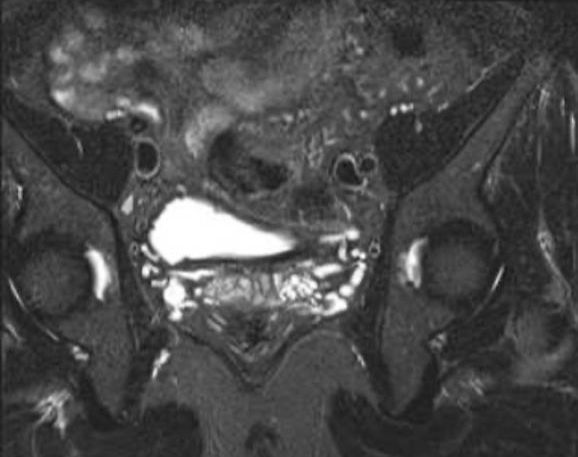

今年初,张先生了解到贵州航天医院泌尿外科相关男科信息,遂前来就诊,完善MRI(磁共振)等检查后,发现左侧精囊内存在结石并伴有炎症。泌尿外科专家团队对此进行了深入讨论,结合患者身体情况排除了相关手术禁忌,征得患者及家属同意后,决定采用精囊镜手术治疗方案。

术中,李国成副主任医师通过细如笔芯的精囊镜,见患者射精管开口喷血,左侧精囊内结石,双侧精囊内黏膜有慢性炎症改变。最终,在精囊镜的导引下,精准定位结石,同步进行冲洗、取石和止血等操作,成功完成手术。

射精管出血

精囊内结石

炎症改变